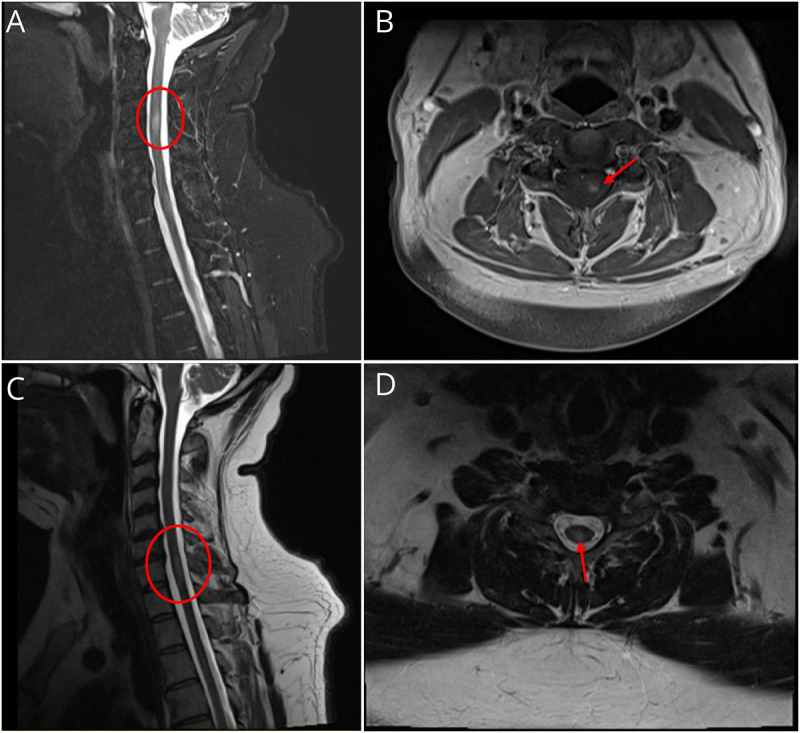

A 46-year-old man presented with progressive painful monocular vision loss and left leg paresthesias. Workup demonstrated multifocal demyelinating lesions and CSF-restricted oligoclonal bands. He was diagnosed with multiple sclerosis (MS), but follow-up testing was notable for positive myelin oligodendrocyte glycoprotein-immunoglobulin G (MOG-IgG). We discuss implications and clinical considerations for MOG-IgG positivity in MS.